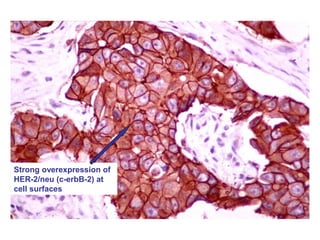

c-erbB-2 (HER-2/neu)

• Oncogene which shares extensive sequence

homology with epidermal growth factor receptor

Strong overexpression of

HER-2/neu (c-erbB-2) at

cell surfaces

c-erbB-2 (HER-2/neu) • Oncogenewhich shares extensive sequence homology with epidermal growth factor receptor (EGFR)

Strong overexpression of HER-2/neu(c-erbB-2) at cell surfaces

BREAST CANCER HER-2/neuHER-2/neu overexpressionoverexpression •There is a significant decrease of 5-year survival in patients whose tumors overexpress HER-2/neu • This decrease in survival for both node-positive and node-negative patients • In vitro studies show that HER-2/neu overexpression increases the following cell activities in malignant breast epithelial cells: DNA synthesis Cell growth Anchorage-dependent growth Tumorgencity Metastatic potential Slamon DJ. Chemotherapy Foundation Symposium. 1999;46. Abstract 39. Goldenberg MM. Clinical Therapeutics. 1999;21(2):309- 318.

• #89 HER-2/neu Overexpression The HER-2/neu proto-oncogene is now known to have prognostic value. Approximately 25% to 30% of all breast cancer patients overexpress HER-2/neu. These patients, whether node-negative or node-positive, have been found to have a significant decrease in 5-year survival rates. In vitro studies have shown that HER-2/neu overexpression increases DNA synthesis, cell growth, anchorage-dependent growth, tumorigencity, and metastatic potential in human breast epithelial cells.